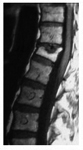

Die weitaus meisten Rückenprobleme sind duch einen relativ früh beginnenden Verschleissprozess der Wirbelsäule bedingt.

Das Verständnis der Symptome soll Ihnen helfen, Ihre Rückenerkrankung besser zu verstehen und damit zeitgerecht zu handeln.